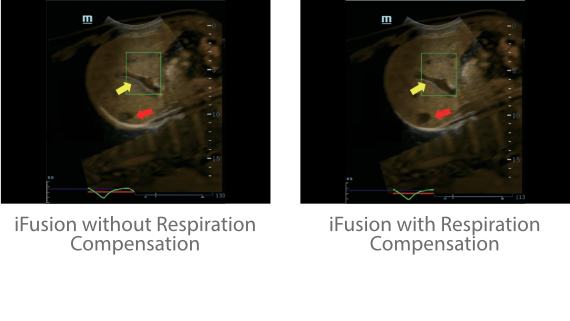

Dank der ZONE Sonography?-Technologie (ZST+) wird das B-Bild des Resona 7 ├╝ber die komplette Tiefe fokussiert, sodass keine Fokuspunkte mehr gesetzt werden m├╝ssen. Die Schall-Lauf-Geschwindigkeit (SSC) wird auf Knopfdruck individuell auf den Patienten angepasst, was die Darstellung von Organen, Grenzfl?chen und Gewebever?nderungen erheblich verbessert. Und dank der fortschrittlichen iFusion-Funktion k?nnen optional die Daten von Ultraschall-, MRT-und CT-Bildern synchronisiert werden.